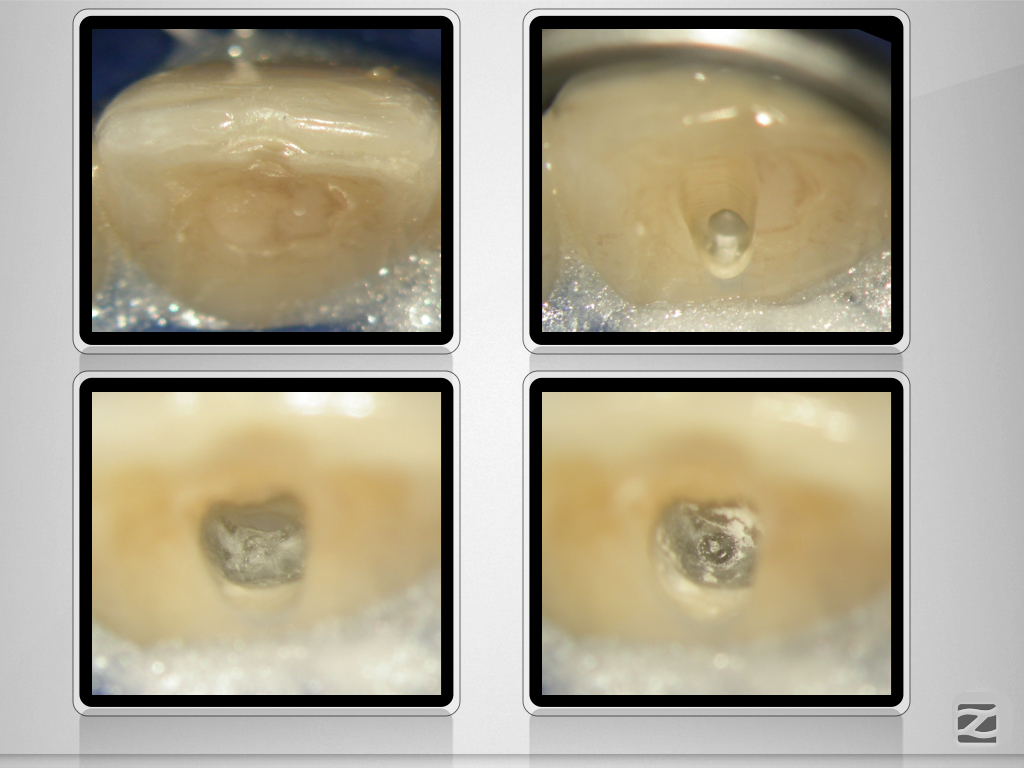

Im zweiten Anlauf – Guided Endo